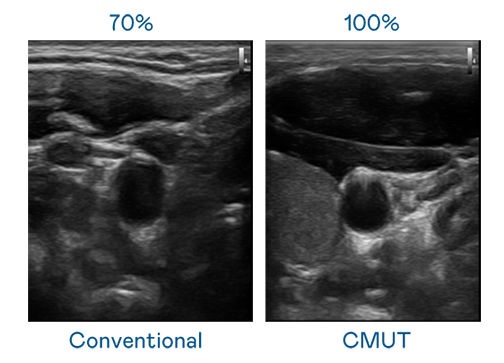

CMUT 技術是一種用電容式微機電元件來產生超音波訊號的技術。與傳統 PZT 壓電式技術相比,CMUT 頻寬增加 30%,更寬頻的超音波訊號讓影像解析度大幅提升,是實現高影像品質醫療超音波掃描、促進精準醫療發展的關鍵技術。

大頻寬帶來超清晰影像

超音波影像的解析度高低,首先取決於探頭能發出的訊號頻寬。友達 CMUT 可提供高清晰的超音波訊號,提供高頻寬、高靈敏度、影像紋理細節更高的超音波影像,協助醫護人員縮短影像判讀時間及利用精準的醫療影像進行診斷。